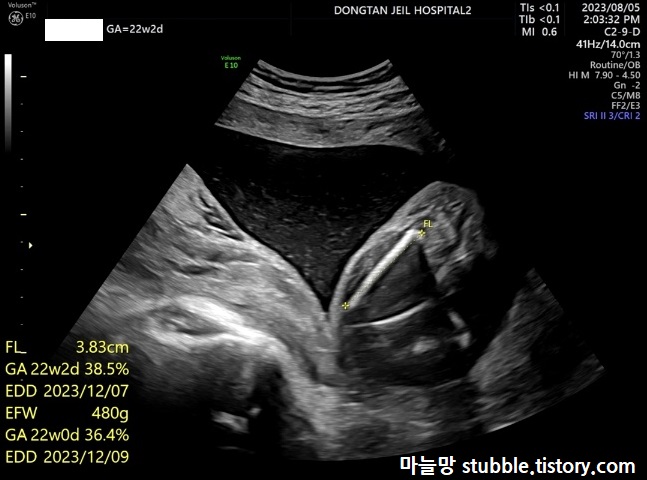

3. 넓적다리 뼈길이 (FL)

언제부터인가 병원가면 항상 재는 거죠? 허벅지 뼈길이입니다.

3.83cm으로 잘 자라고 있었어요.

4. 아기 예상 몸무게 (EFW)

아기 예상 몸무게는 EFW라고 하는데, 뼈길이등을 종합하여 예상 몸무게를 산출합니다.

초음파상에 같이 나옵니다. (EFW = 480g) 거의 500g 정도로 많이 컸어요.